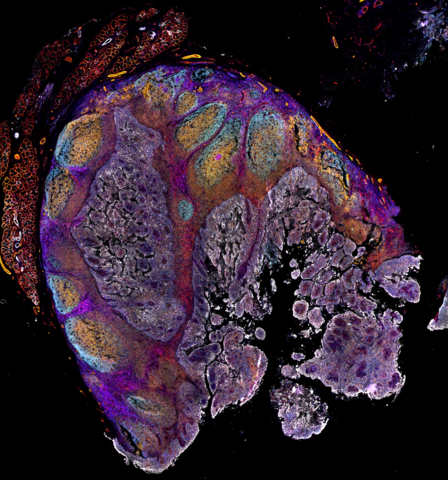

WALTHAM, Mass.--(BUSINESS WIRE)--Thermo Fisher Scientific Inc., the world leader in serving science, today introduced the Invitrogen™ EVOS™ S1000 Spatial Imaging System. This advanced system addresses the limitations of current fluorescent microscopy technologies by enabling researchers to generate a multiplexed high-quality image for multiple samples within several hours, thereby lowering the barrier to entry into spatial tissue proteomics.

The EVOS S1000, from Thermo Fisher Scientific’s innovative line of cell imaging microscopes and systems, leverages advanced and patented spectral technology, allowing researchers to capture images of up to 9 different targets simultaneously, which helps reduce the need for multiple rounds of imaging and preserves tissue integrity.

"Understanding tissue structure and function is crucial for developing new treatments for solid tumors and neurodegenerative diseases," said Trisha Dowling, vice president and general manager for flow and imaging technologies at Thermo Fisher Scientific. “The EVOS S1000 delivers a detailed snapshot of tissue microenvironments and architecture in their native state, helping researchers accelerate their experiments, achieve more with their tissue samples and drive advancements in critical research areas."